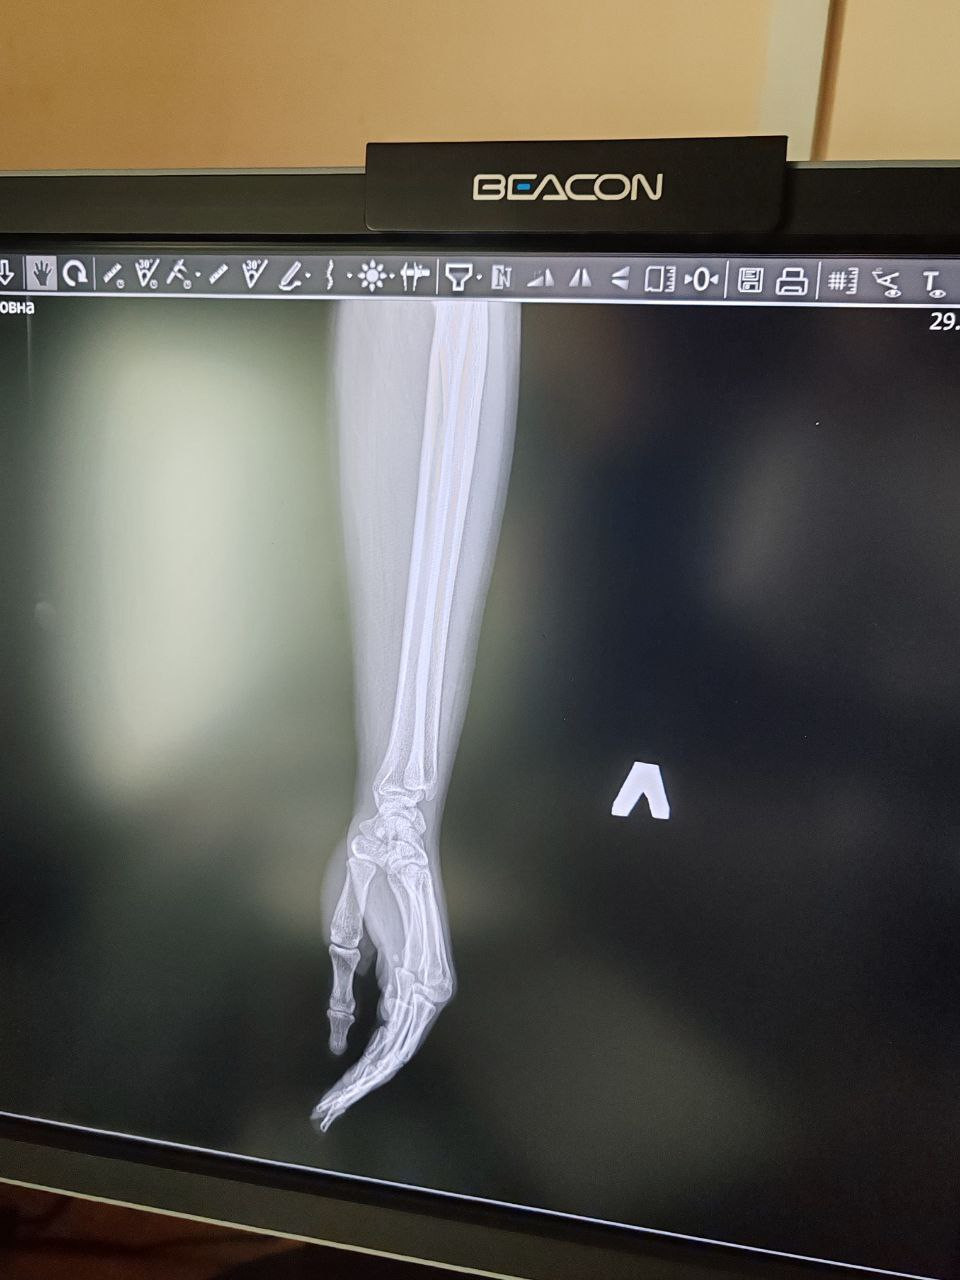

Здравствуйте, 28.01 ударила руку сначала рука не сильно болела, а теперь с каждым днём всё хуже, 29.01 сделали снимки врачи в травмпункте утверждают что просто ушиб , ранее 2 года назад мне ставили дисторсию лучезапястного сустава и я ходила в гипсе , сейчас же при очень сильных болях рекомендаций никаких нету , рука опухшая, больно шевелить , прикреплю снимки рентгена, надеюсь на вашу помощь , скажите пожалуйста что нужно делать (меня смущает на снимке расстояние между косточками) так же часто немеют пальцы и ощущается пульс в руке

Здравствуйте. По снимкам явного перелома не видно, но описанные боли, отёк, онемение и «расстояние между косточками» могут указывать на повреждение связок лучезапястного сустава. Для уменьшения боли сейчас нужна фиксация кисти ортезом или бинтом, покой, холод 2-3 раза в день и НПВС по возрасту. Обязательно повторный осмотр травматолога, при необходимости МРТ т.к связочные травмы на рентгене часто не видны. Можно УЗИ  оно позволяет оценить связки, сухожилия и наличие отёка. Но при сохраняющейся сильной боли и онемении МРТ информативнее.